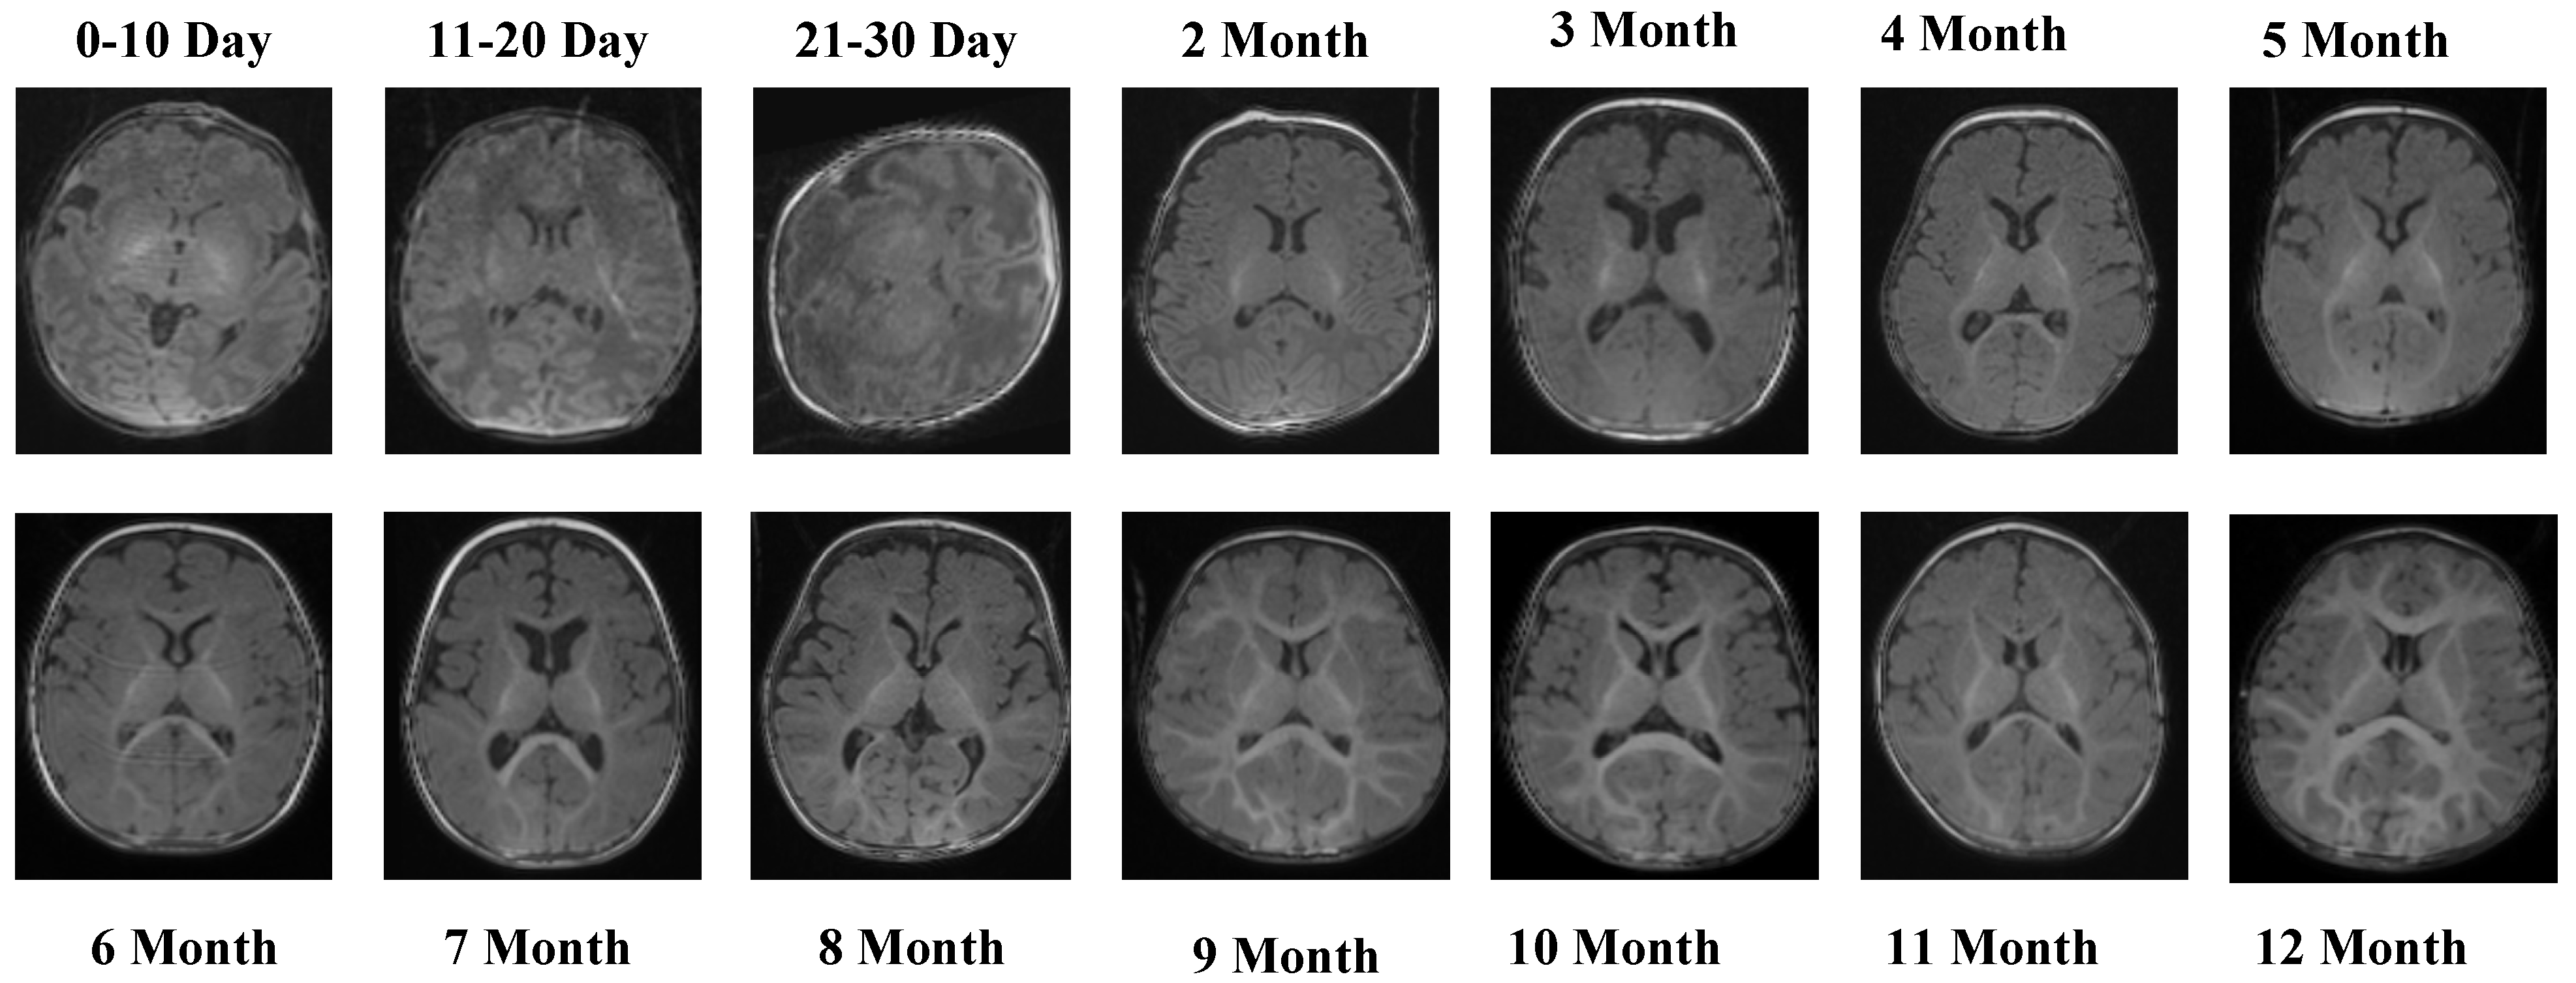

Figure 2 presents representative MRI slices from the T1 Female sequence, demonstrating structural variability across neonatal and infant stages.

The T1 Female sequence comprised 7754 images, with 6205 used for training and 1549 for testing. Similarly to the male subset, the data follow the same chronological structure, ensuring comparability across sexes. This facilitates a robust evaluation of potential sex-specific developmental differences. Representative samples from the T2 Male sequence are provided in Figure 3, highlighting the contrast-specific features of T2-weighted imaging across developmental stages.